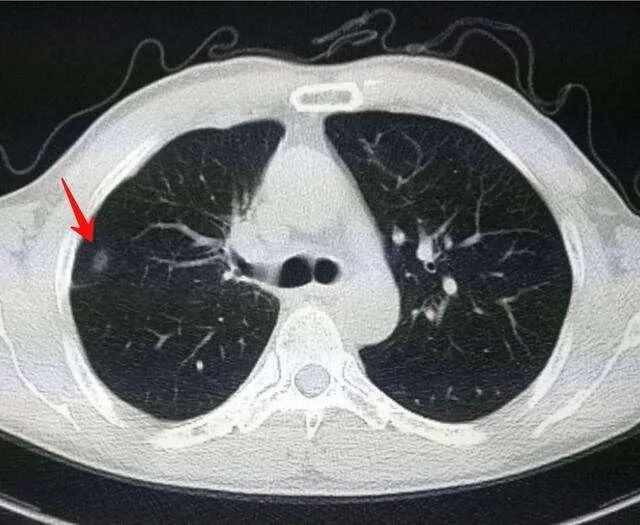

这位患者姓陈,是一位军转退休干部,2014年查出肺结节后,因为结节只有0.6公分大小,医生建议随访,因为没有什么治疗办法,老先生便一直定期复查,并开始收集有关孙彩珍院长中医治疗肿瘤的报道。

但是陈先生的肺结节这6年来,悄无声息地长大着,如今已经到1公分了。考虑到自己年纪大了,这么多年看到很多肺结节患者吃中药得到了控制,甚至有消失的案例,所以他也不想去做穿刺检查,所以要求来吃中药控制肺结节的发展。